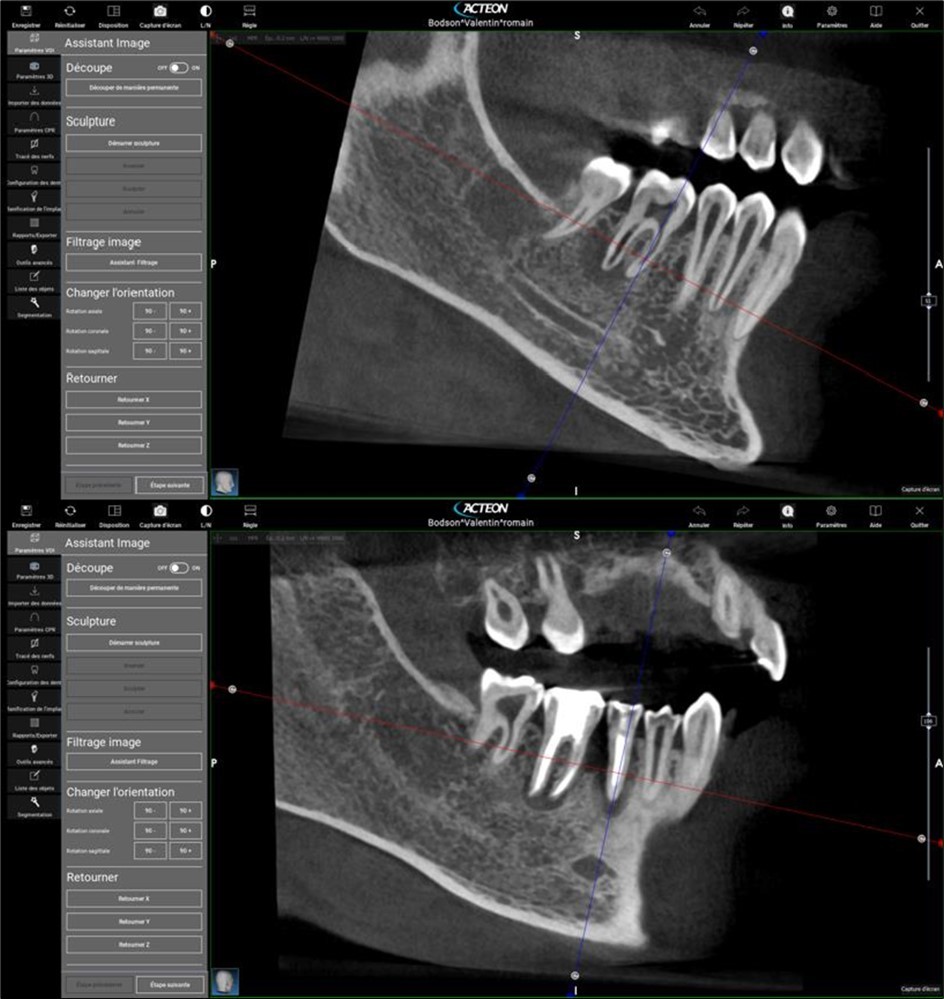

Periapical radiography (phosphorus number 2 plaque and X-MIND® Unity; Acteon) and cone-beam computed tomography (X-MIND® 3D; Acteon) (80 × 80, 150 Micron) were performed and showed periapical lesions on teeth 14, 15, 16, 24, 25, 26, 35, 36, and 46, as well as advanced endo-perio lesions on teeth 26 and 16. orthopantomogram (X-MIND® 3D; Acteon) and bitewings (phosphorus number 2 plaque and X-MIND® Unity; Acteon) also showed wide pulp chambers and roots canals. Figure 1, Figure 2

Figure 1.1 and 2 show a wide pulp chamber, root canals, and several restorations.

Figure 2.2. 3, 4, and 5 show periapical lesions on teeth 15, 16, 24, 25, 26, 35, 36, and 46.